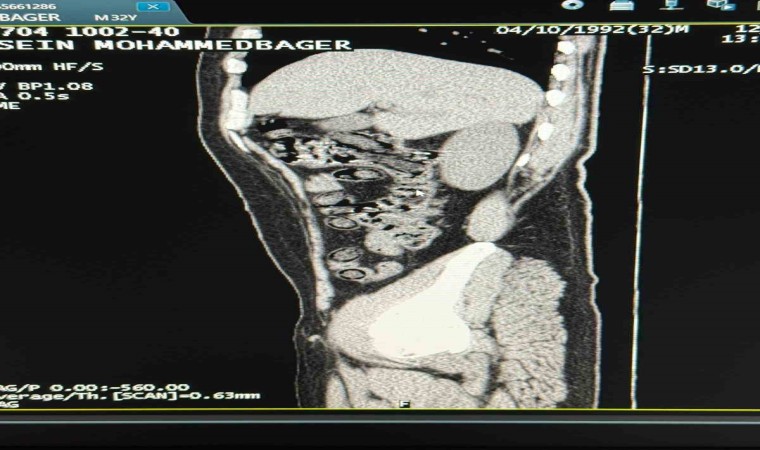

Muş Valiliği tarafından yapılan açıklamada, “Narkotik Suçlarla Mücadele Şube Müdürlüğümüzce uyuşturucu madde sevkiyatına engel olmak için yapılan çalışmalar neticesinde İran uyruklu 2 şahsın şehirlerarası yolcu otobüsü ile illere uyuşturucu madde nakli gerçekleştirebilecekleri değerlendirilmiş, 6 Aralık günü saat 11.30 sıralarında şüpheli şahısların görevlilerimizce yapılan sorgulamasında uyuşturucu madde naklettikleri yönünde kuvvetli şüphe oluşmuştur. Hastanede yapılan iç beden muayeneleri sırasında çekilen tomografi görüntülerine göre uyuşturucu madde yuttukları tespit edilmiştir. Hastanede yapılan tespit sonrasında şahısların midelerinde toplam 94 adet kapsül içerisinde daralı ağırlıkları 928 gram gelen metamfetamin maddesi ele geçirilmiştir. Şüpheli şahıslar hakkında ‘uyuşturucu ve uyarıcı madde ticareti’ suçundan işlem yapılmak üzere Cumhuriyet Başsavcılığına intikal ettirilmiş ve çıkarıldıkları mahkemece tutuklanmışlardır” denildi.